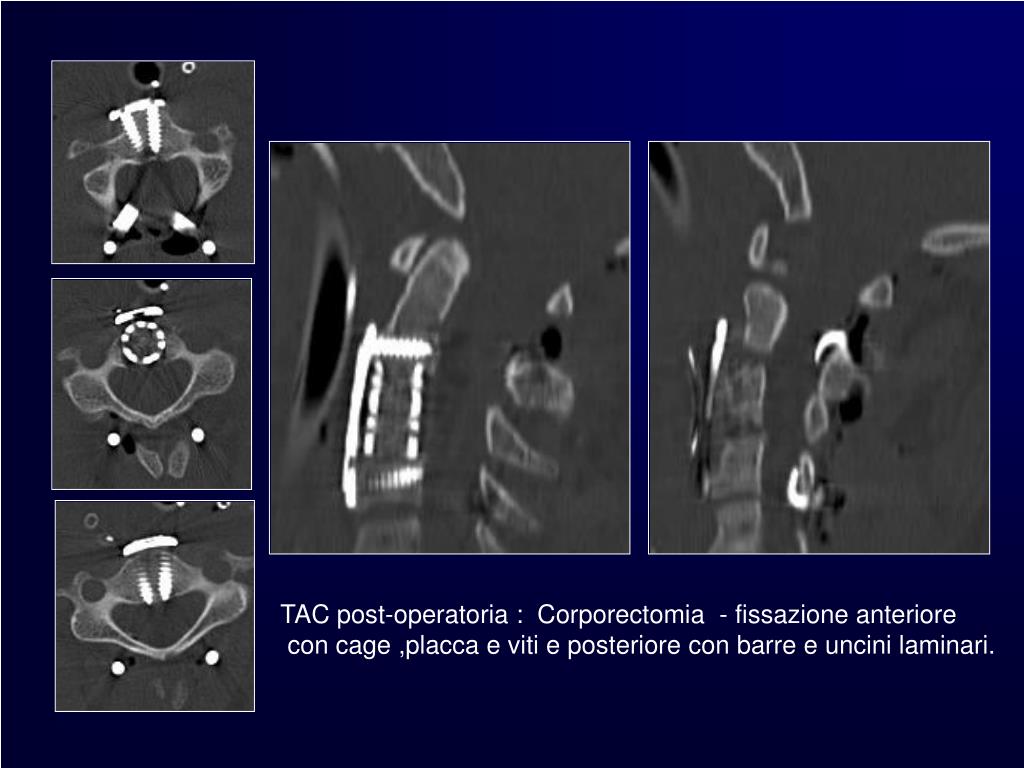

12. TAC post-operatoria :Corporectomia- fissazione anteriore con cage ,placca e viti e posteriore con barre e uncini laminari.